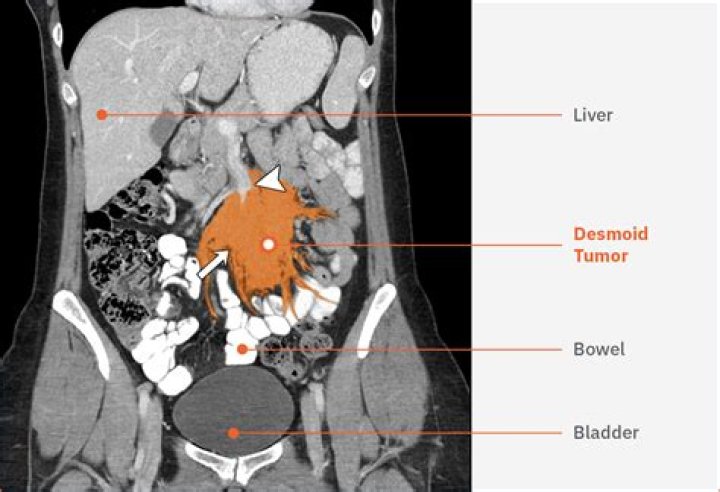

Desmoid tumors are also known as aggressive fibromatosis or desmoid-type fibromatosis. A desmoid tumor can occur anywhere in the body since connective tissue is found everywhere in your body. Desmoid tumors are often found in the abdomen, as well as the shoulders, upper arms, and thighs.

Doctors use imaging to detect desmoid tumors. An MRI or CT scan can show how extensive the tumor is. Desmoids rarely spread to other parts of the body, but they can grow in multiple locations. A biopsy is required to be sure of the diagnosis.